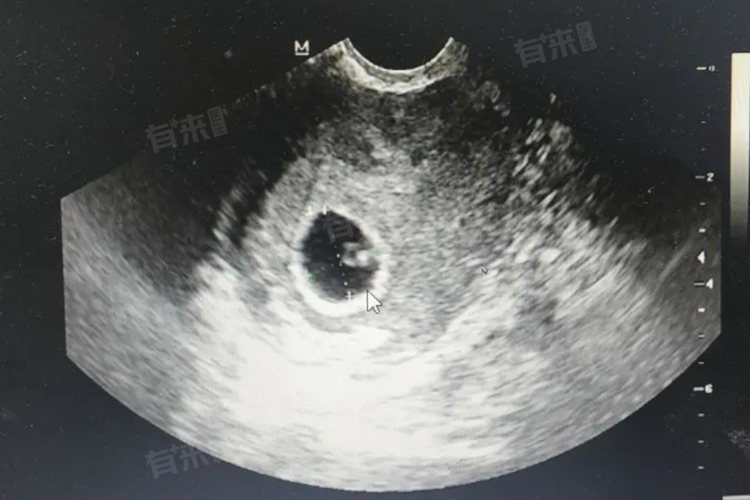

- 在人类中,胚胎期通常指的是从受精后的第2周到第8周。在这一时期,胚胎的外形和内部结构发生了巨大的变化。通过胚胎的发育,可以观察到心脏的形成和跳动、四肢的雏形出现等重要的发育事件。